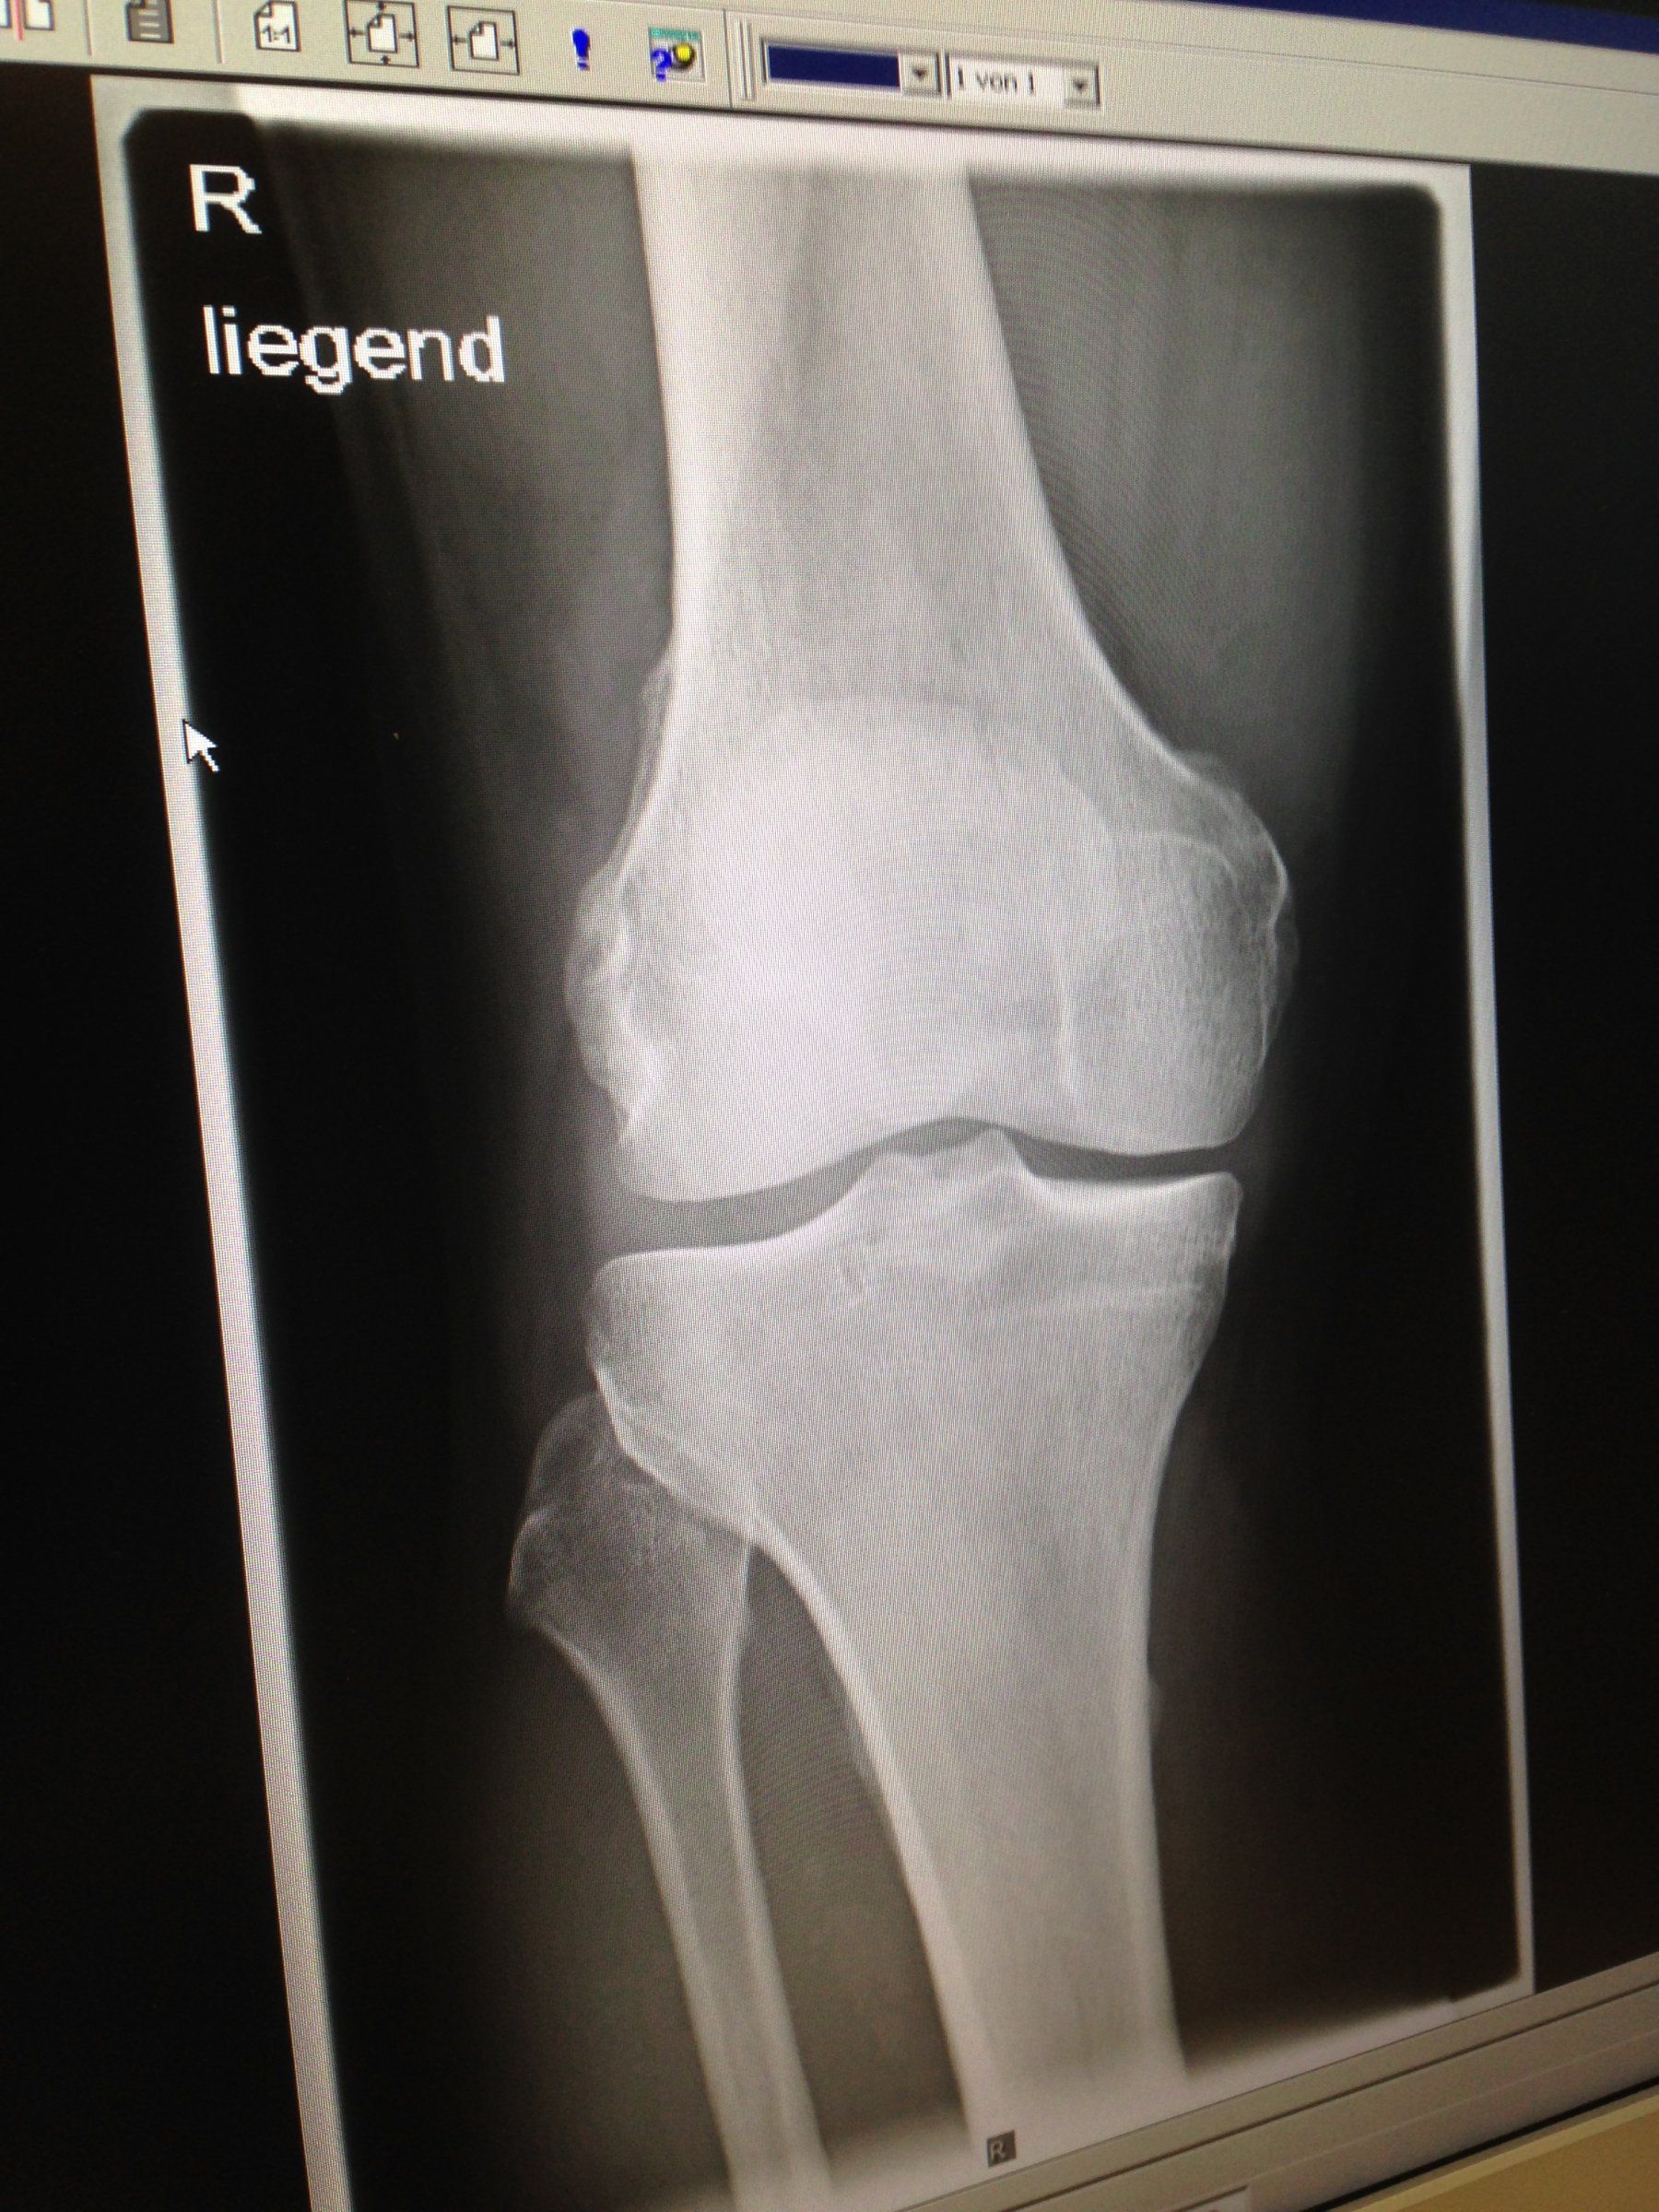

Ich mache mir da jetzt gar keinen Kopf. Die Knochen selber sind in Ordnung, alle Knochenabstände (auch zur Kniescheibe) sind noch korrekt und es gibt keinen erwähnenswerten Abnutzungsgrad. Das wäre nämlich meine größte Sorge gewesen.

Verdacht auf Innenmeniskusläsion: Das gibt zwei kleine Löcher im Knie und nach maximal einer Woche heißt es wieder "Kette rechts" (... oder links)

Gute Besserung und hoffentlich wird aus Optimismus Realität. Unmöglich ist es nicht: der Patient vor mir spielte vier Wochen nach seiner Meniskus-OP schon wieder Fußball - und das belastet das Knie doch deutlich mehr als Radfahren. Aber "Kette links" wäre am Anfang wirklich keine schlechte Idee ;).